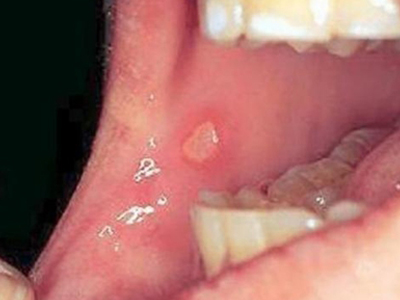

口腔溃疡为圆形或椭圆形,直径0.2-0.5cm,溃疡单个或由数个连成一片,溃疡表浅边缘整齐,外观呈灰黄色或灰白色,上覆盖黄白渗出膜,周围黏膜充血、水肿而有红晕。

皮损局部有烧灼样疼痛,于进餐时加重,影响进食、说话。严重溃疡直径可达1-3cm,深及黏膜下层甚至肌肉。